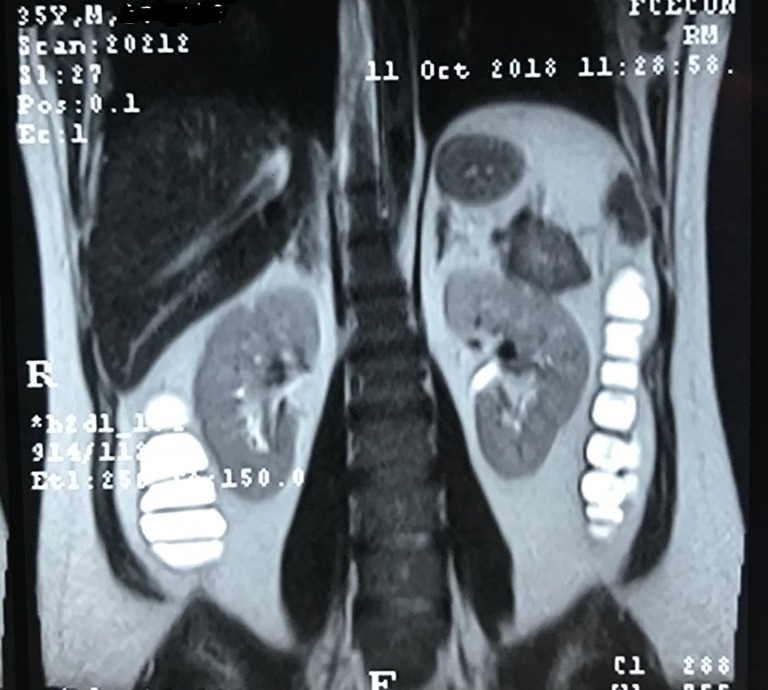

Figure 3.

Coronal section abdominal and pelvic tomography, with oral and intravenous contrast, with pancreatic tail injury image.

Subsequently, the patient was subjected to treatment with prednisone daily and mesalazine but presenting allergic manifestations to the latter. Abdominal magnetic nuclear resonance (MRI) and abdominal computed tomography (CT) were made, showing a solid tumor with enhancement after contrast of 4.8 cm × 4.0 cm in the pancreas tail. He was discharged after hydro electrolytic correction, with a referral to the outpatient surgery for digestive tract surgery (Figures 1-3). Dosages of various elements were requested to define a diagnosis, such as glucagon, somatomedin C, basal insulin, gastrin, and serum intestinal vasoactive peptide (VIP). From these, only VIP had high values (119.8 PMOL/L; reference value up to 30 PMOL/L), leading to the suspicion of VIPoma, neuroendocrine pancreas tumor with VIP production, which could influence the worsening of diarrheal condition alternatively, until it started.

The diagnosis is made only by combining these estimates with a VIP greater than 75 pg/mL consistent for a VIPoma. Imaging is essential for diagnosing the disease and thus enabling more effective treatment. To do so, it recommends PET-CT Gallium-68 dotatate, which has 97% detection of VIPomas other than contrast-enhanced computed tomography (80%) and magnetic resonance imaging (85%) that have long been used in the medical examination so far (2). In our study, the tumor side was 4.0 cm × 4.8 cm at the tail of the pancreas, finding computed tomography and nuclear magnetic resonance of the abdomen and pelvis, and there are no signs of metastatic disease.